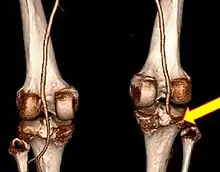

CT angiogram 3D reconstruction, posterior view showing a normal artery on the left, and occlusion to right popliteal artery as a result of a knee dislocation[10]

Complications may include injury to the artery behind the knee (popliteal artery) in about 20% of cases or compartment syndrome.[3][4] Damage to the common peroneal nerve or tibial nerve may also occur.[2] Nerve problems, if they occur, often persist to a variable degree.[11]